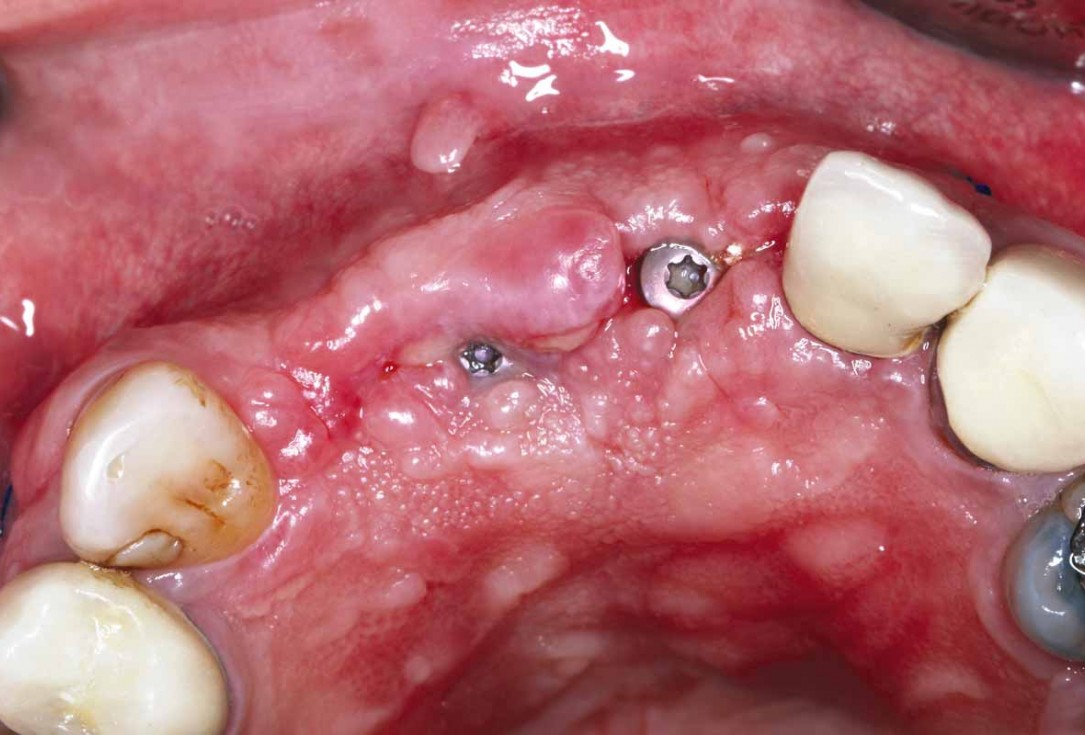

16/27 - 12 weeks after surgery: showing partial exposure of the healing abutments and satisfactory convexity

GBR and soft tissue augmentation with cerabone® and mucoderm® - H. Maghaireh & V. Ivancheva

17/27 - Occlusal view